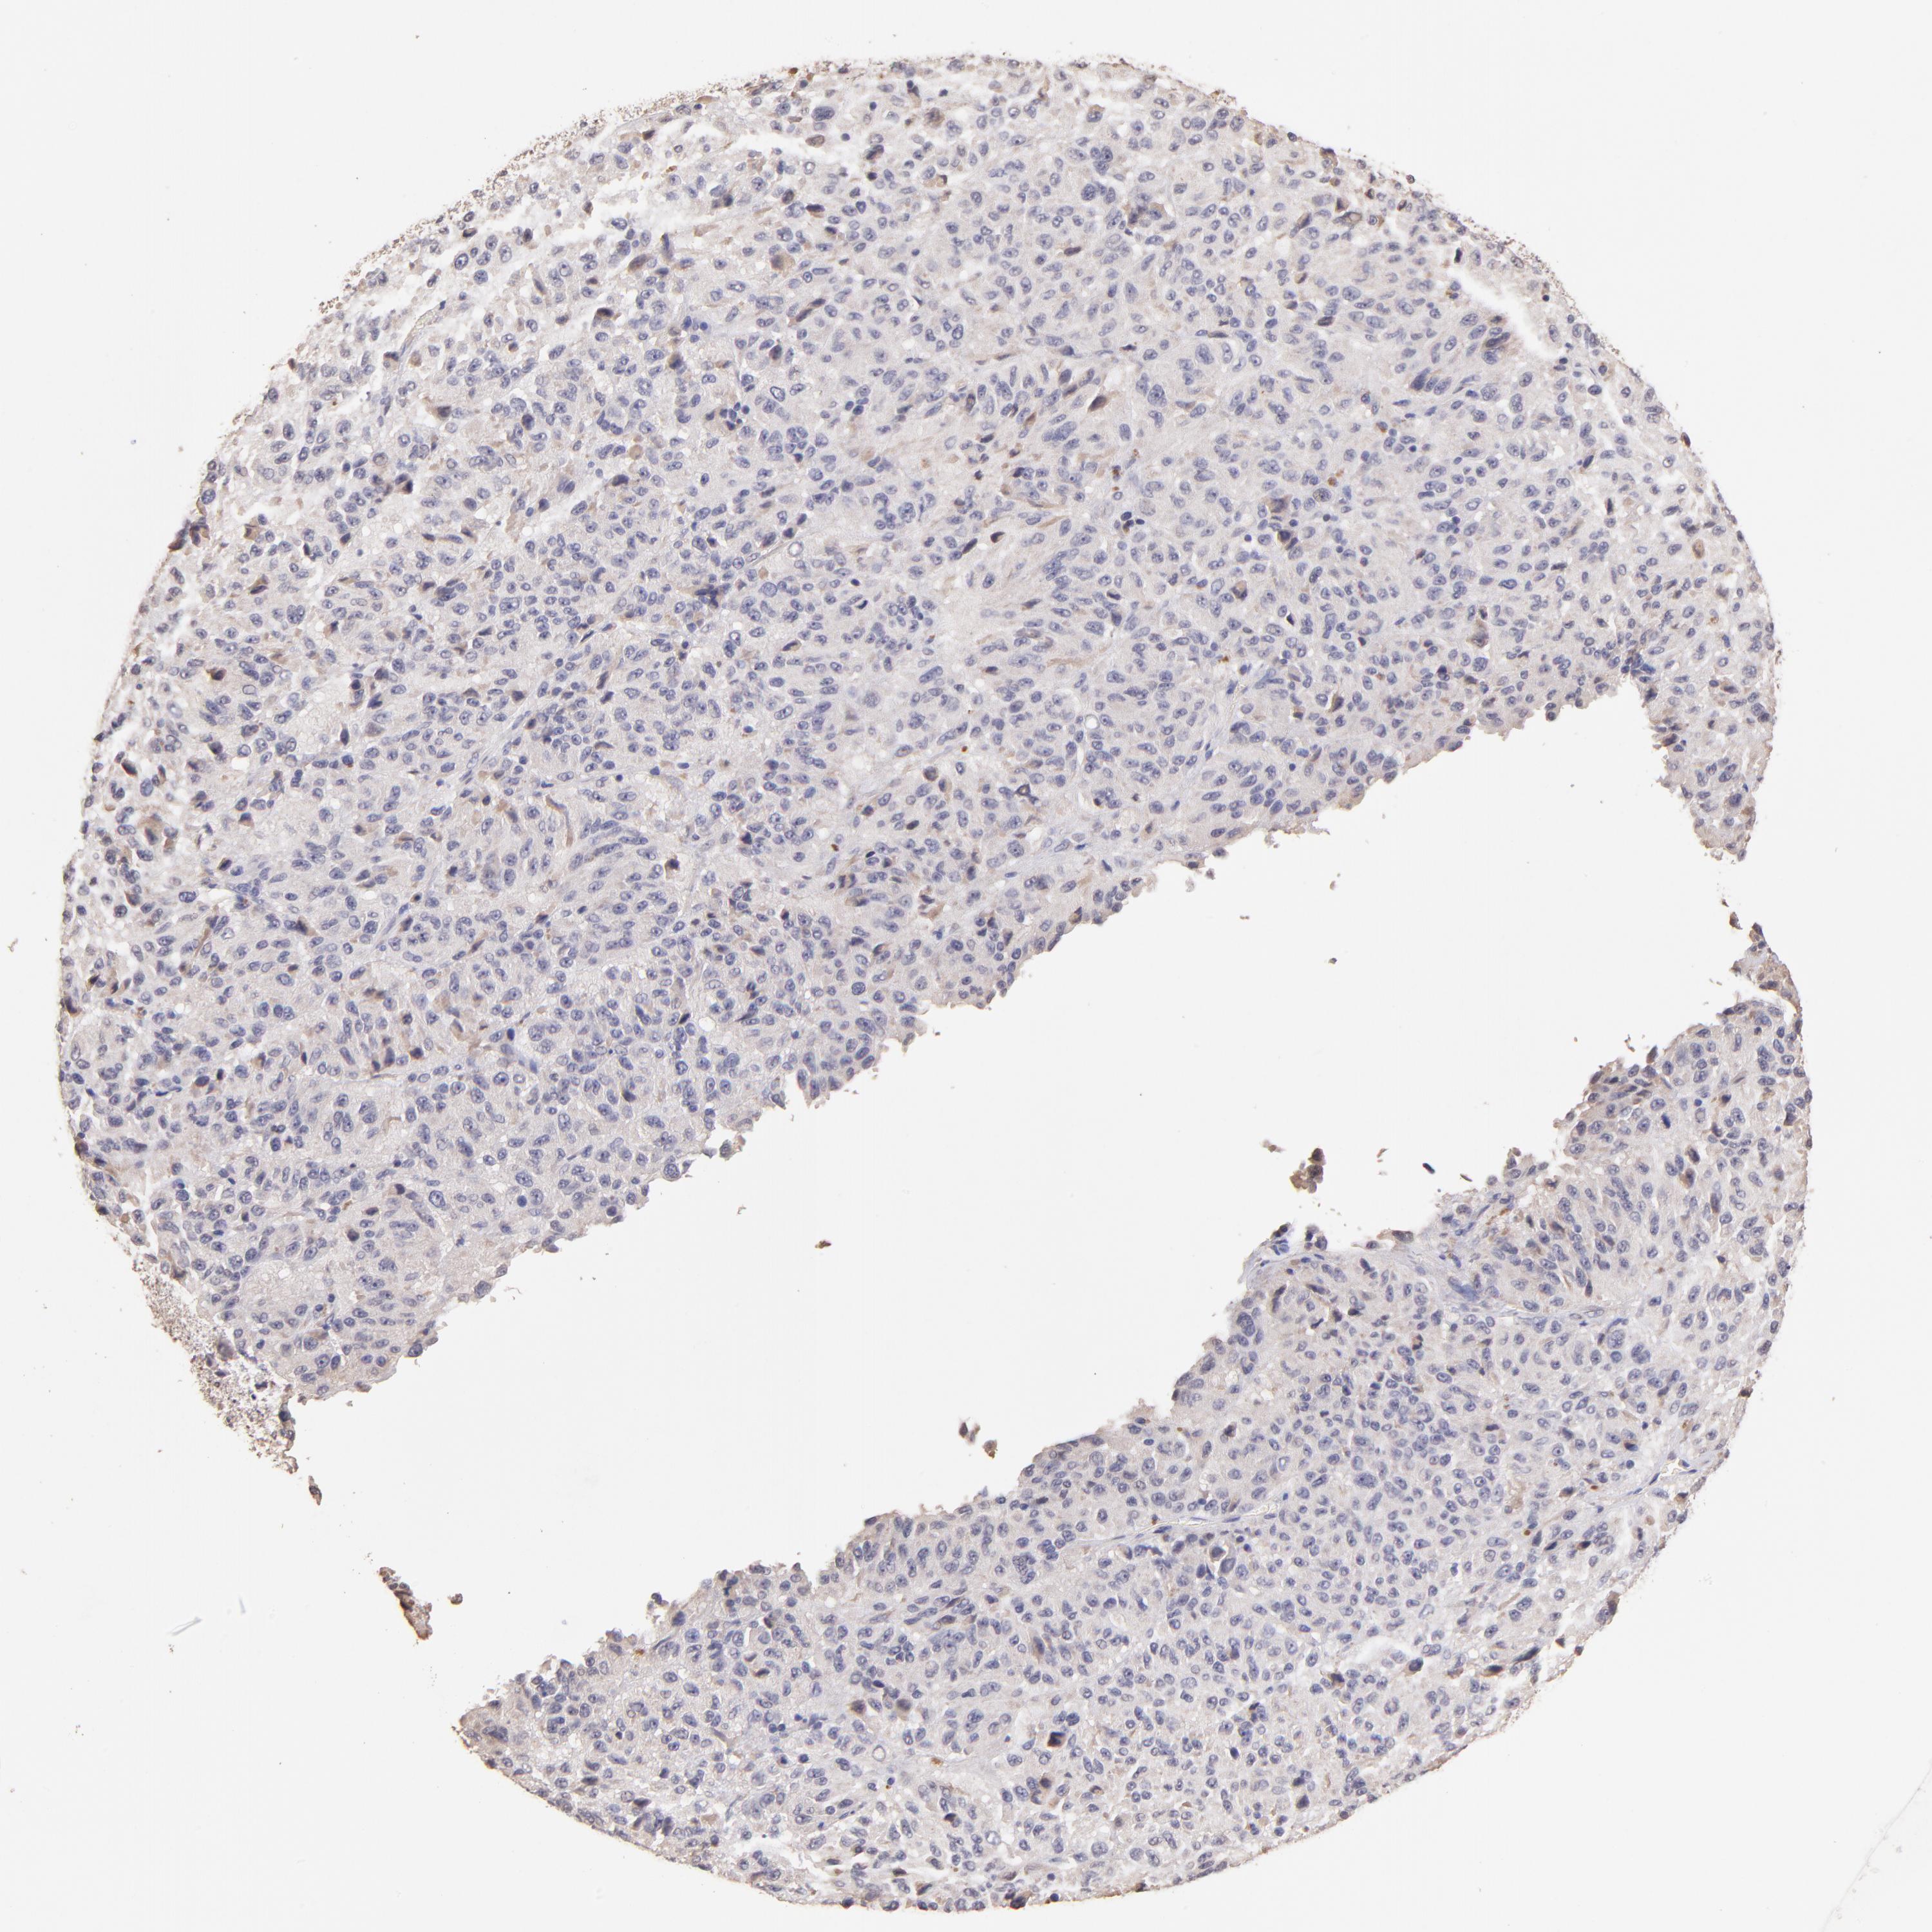

MELANOMA - Protein expressioni

A mouse-over function shows sample information and annotation data. Click on an image to view it in a full screen mode. Samples can be filtered based on level of antibody staining by selecting one or several of the following categories: high, medium, low and not detected. The assay and annotation is described here.

Note that samples used for immunohistochemistry by the Human Protein Atlas do not correspond to samples in the TCGA dataset.

Antibody stainingi

Antibody staining in the annotated cell types in the current human tissue is reported as not detected, low, medium, or high, based on conventional immunohistochemistry profiling in selected tissues. This score is based on the combination of the staining intensity and fraction of stained cells.

Each image is clickable and will lead to virtual microscopy that enables deeper exploration of all samples and also displays staining intensity scores, fraction scores and subcellular localization as well as patient and tissue information for each sample.

Antibody HPA002633

Antibody HPA046758

Antibody CAB010906

Staining

High

Medium

Low

Not detected

Intensity

Strong

Moderate

Weak

Negative

Quantity

>75%

75%-25%

<25%

None

Location

Nuclear

Cytoplasmic/membranous

Cytoplasmic/membranous,nuclear

Malignant melanoma, NOS

Malignant melanoma, Metastatic site

Malignant melanoma in situ